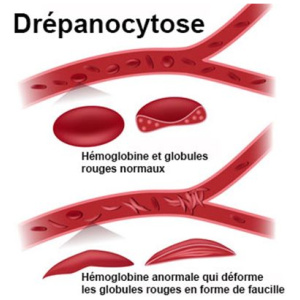

Consultation / Traitement Anti-drépanocytose

- 27.500,00 CFA

- Acheter

- Santé humaine